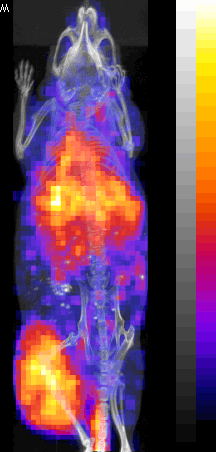

PET/CT Images

Nude mouse with a SUM190 tumor received intravenous antisense (anti-RIa)

18F-MORF/tat/Herceptin nanoparticle and PET/CT images obtained at at 3 and 8 hr.